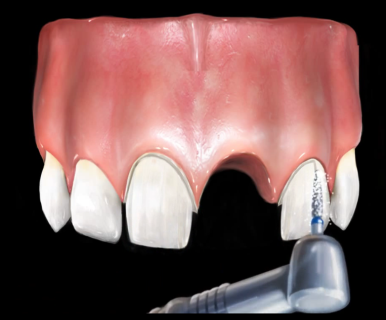

뺀 치아의 양 옆 치아를 깎아서 3개 이상의 머리를 걸게 됩니다.

이번에는 저희 치과를 찾아오신 외국인 환자분의 앞니 브릿지 치료 사례를 한번 보겠습니다.

방금 넘어져서 앞니가 깨졌다며

잘하는 치과 수소문해서 소개받고 오신 외국인환자분입니다.

처음에는 크라운을 하면 될거라 예상했지만

자세히 보니 앞니가 뿌리 부분까지 쪼개져서 벌어져 있었습니다.

발치해서 보니 위와 같이 잇몸 깊은 곳까지 두동강 나 있어서

살리기 힘든 상태였습니다.

발치를 하였고 치아를 빼면 구멍이 생기니

잇몸이 아무는데까지 기다렸다가 브릿지를 해야 합니다.

어차피 양 옆 치아도 많이 썩어있었기 때문에 임플란트 보다는 브릿지를 하기로 하였습니다.